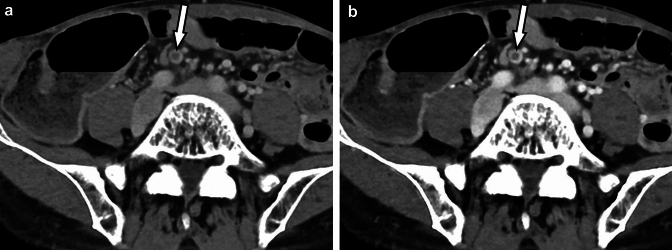

Fig. 8.

Pancreatic cancer is shown as a small hypovascular nodule in the tail of the pancreas (arrows) on the pancreatic parenchymal phase (arterial phase) photon-counting CT images at 70 (A) and 50 keV (B). Meanwhile, enhancement of the tumor (arrows) is shown during the equilibrium phase at 70 (C) and 50 keV (D). The delayed enhancement is more evident in the 50 keV image (D) than in the 70 keV image (C). Small pancreatic cancers are often not visualized in the pancreatic parenchymal phase but are visualized as delayed-enhancement lesions only in the equilibrium phase. Low-keV images obtained with photon-counting CT may help in the early detection of pancreatic cancer